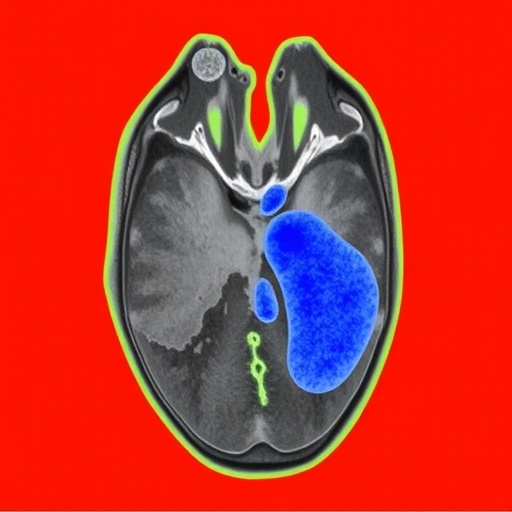

In the rapidly evolving landscape of medical imaging and artificial intelligence, a groundbreaking advancement has emerged that promises to enhance the clinical management of ischemic stroke. A recently developed deep learning model, known as DeepISLES, has been meticulously engineered and clinically validated to substantially improve the precision and efficiency of ischemic stroke lesion segmentation. Originating from the rigorous benchmarking efforts led by the ISLES’22 challenge, this innovative approach is set to revolutionize how clinicians assess and intervene in acute stroke cases.

Addressing these challenges, DeepISLES employs state-of-the-art deep convolutional neural networks (CNNs) and advanced image processing techniques to deliver robust ischemic lesion segmentation. The architecture integrates several layers of feature extraction, enabling the model to differentiate intricate tissue characteristics and pathological variations that correspond to stroke injuries. By leveraging a large and diverse multinational training dataset provided by the ISLES’22 challenge consortium, DeepISLES achieves remarkable generalizability across various imaging protocols and patient demographics.

DeepISLES incorporates multi-modal imaging inputs, primarily fluid-attenuated inversion recovery (FLAIR) and diffusion-weighted imaging (DWI) sequences, which provide complementary insights into the ischemic tissue state. The fusion of these imaging modalities within the neural network framework allows the model to better distinguish between acute infarcts and chronic ischemic changes, a well-known challenge in stroke imaging. This capability not only aids in acute stroke diagnosis but also offers potential utility in tracking lesion evolution during patient recovery and rehabilitation.

From a technical perspective, DeepISLES is constructed on advanced deep learning frameworks with attention mechanisms that highlight salient features within ischemic regions. This approach mitigates false positives that commonly arise in stroke segmentation due to overlapping signal intensities with other pathologies or artifacts. Moreover, the model’s probabilistic output permits threshold adjustments, allowing clinicians to tailor sensitivity and specificity thresholds depending on individual patient contexts or institutional protocols.

The model’s performance metrics are compelling. DeepISLES achieved dice similarity coefficients—a measure of overlap between predicted and ground truth segmentations—that are among the highest reported in the literature for automated ischemic stroke lesion segmentation. It demonstrated high sensitivity in detecting even small, subtle lesions that are often missed in routine clinical practice, a factor crucial for timely therapeutic interventions.